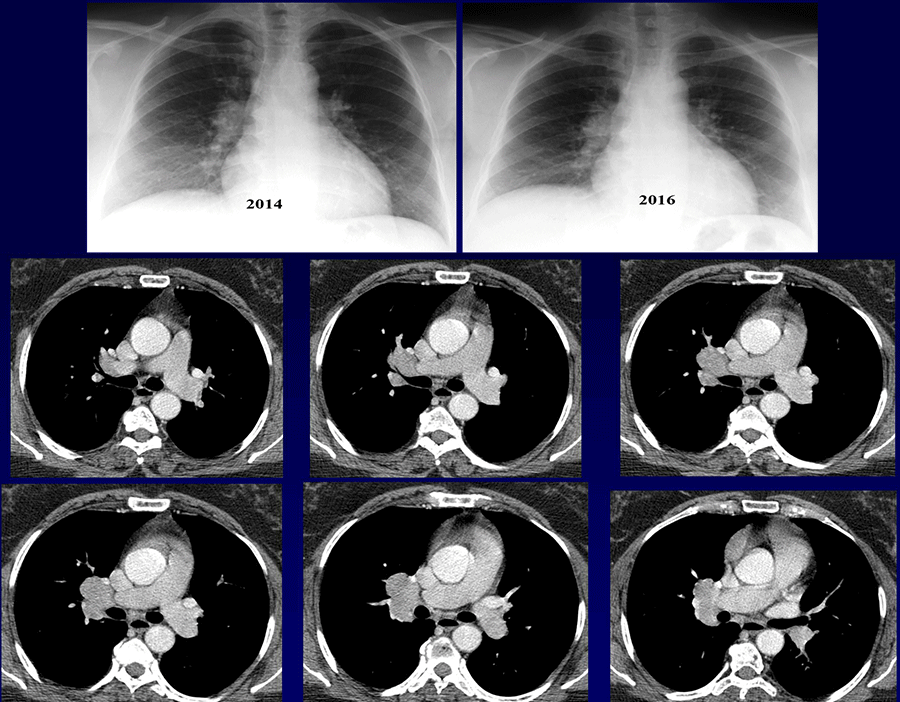

Patiente âgée de 49 ans non tabagique

consulte pour toux sèche évoluant depuis 6 mois

Bon état général

Fibroscopie bronchique : pas de lésion endo bronchique

QUEL EST VOTRE DIAGNOSTIC ?

A – Lymphome

B – Maladie de Castelman

C – Paragangliome

D – Sarcoïdose

E – Autre